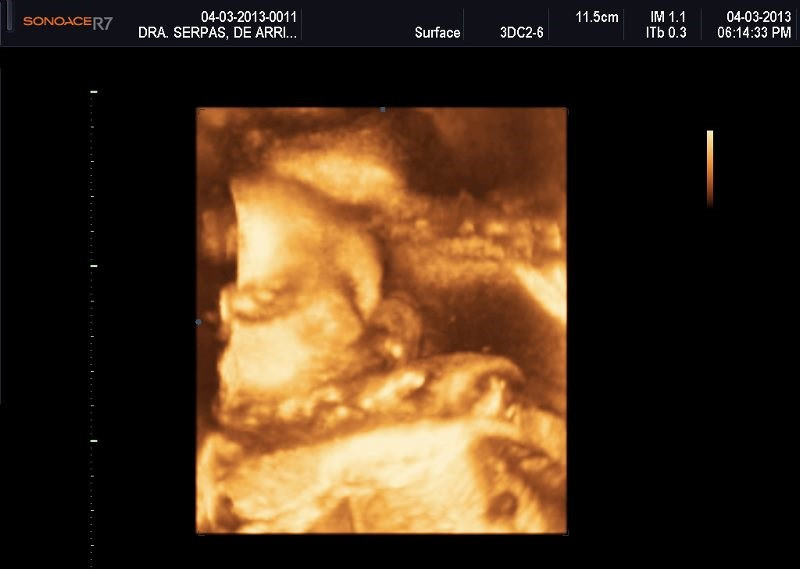

Varias ultrasonografías en 2D y 3D

Envíado por Dr. Nelson Menjívar Sarco